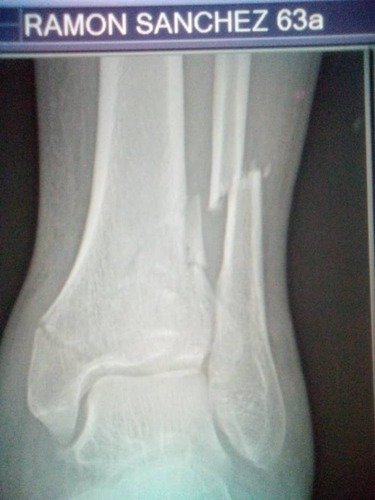

Eu Sou Ramon Sanchez e moro aqui no Brasil ha muitos anos. Sai do meu pais, exatamente no ano 1999. Deixei a Venezuela, meus familiares e meus amigos para servir a Deus no movimento cristão missionário mundial. Criei esta vaquinha com objetivo de poder arrecadar uma ajuda para meu Pai: Seu Ramon Sanchez tem 64 anos (ele esta na foto acima com a camiseta vermelha tirada em 2001). Ele teve uma fratura no tornozelo o que deveria de forma urgente fazer uma cirurgia.

A situação social e política da Venezuela não é novidade para muitos aqui no Brasil, todo este processo tem feito uma crise muito forte o que faz que tudo seja difícil na questão da saúde. Para meu pai fazer esta cirurgia requer comprar os componentes para a reparação da tíbia tornozelo e perônio – Deixarei algumas imagens aqui. como raio X –